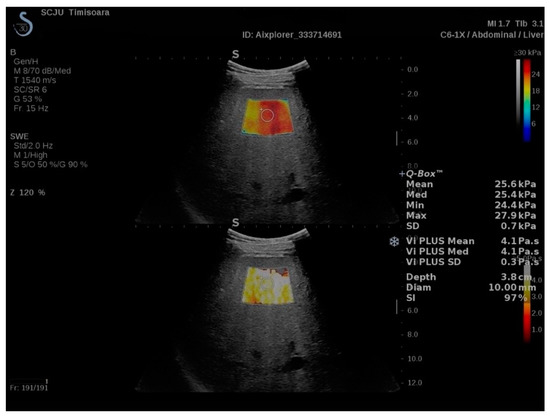

2.2. ShearWave PLUS Elastography

2.3. Viscosity PLUS